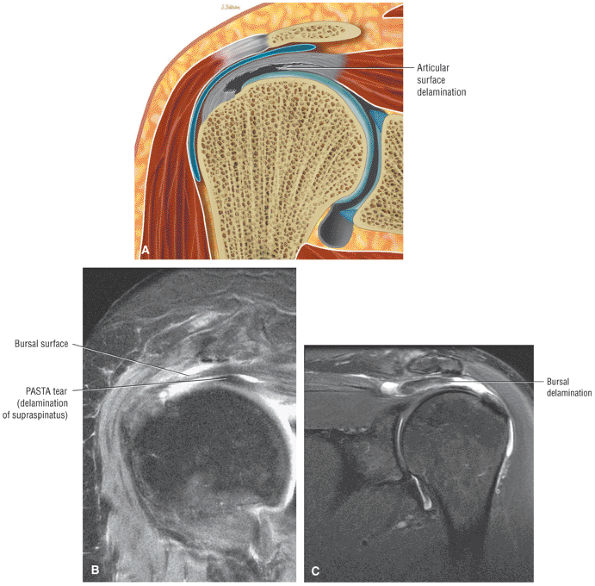

FIGURE 8.102 ● (A) The anterior undersurface of the acromion and the coracoacromial ligament form the coracoacromial arch. The subacromial subdeltoid bursa facilitates the passage of the rotator cuff and proximal humerus under the coracoacromial arch. (B) A superior axial image shows the anterior-to-posterior extent of the coracoacromial (CA) ligament perpendicular to the supraspinatus tendon. The fluid in the subacromial-subdeltoid bursa represents fluid between two serosal surfaces in contact with each other. One serosal surface is contributed by the undersurface of the coracoacromial arch and deltoid, and the other serosal surface is on the bursal side of the cuff.

![]() |

FIGURE 8.103 ● Pseudospur. The normal broad attachment of the coracoacromial ligament to the inferior surface of the acromion is shown on (A) T1-weighted coronal oblique and (B) sagittal oblique images. The low-signal-intensity acromial cortex (black arrows) and adjacent coracoacromial ligament and lateral slip of the deltoid attachment (white arrows) give the false impression of a small subacromial spur in the coronal plane. This pseudospur should not be misinterpreted as impingement; otherwise, unnecessary acromioplasties may be performed on patients with a normal coracoacromial ligament attachment and no associated acromial spurs.

-